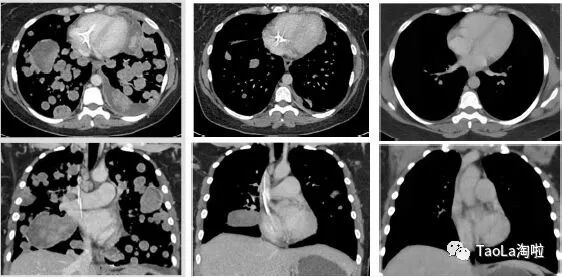

胃肠间质瘤:

55岁男性

治疗前:癌细胞几乎已经扩散到整个肠胃和腹腔

治疗后:接受了9个周期治疗后奇迹出现,肿瘤明显缩小,目前正在接受第10周期治疗。

未分化肉瘤

41岁女性

治疗前:患者的肿瘤细胞已广泛转移到肺部,很快要填满肺部了。

治疗后:迅速解决呼吸困难和低氧血症。2个周期后,大部分肿瘤消失,12个周期后,肿瘤组织几乎完全消失!